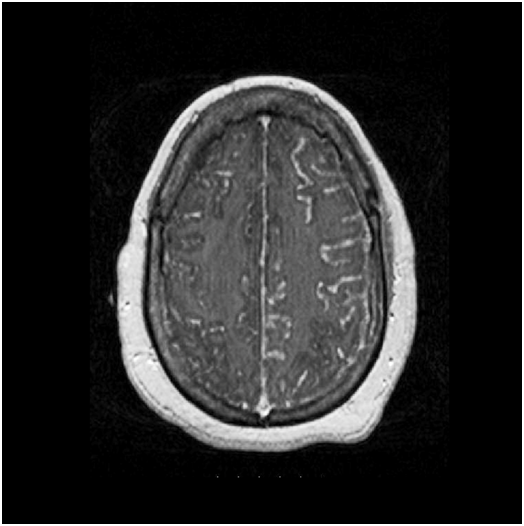

52-year-old African American female presented to our facility with altered mental status. Her past medical history was significant for Neurosarcoidosis, Diabetes Mellitus, Epilepsy and Hypertension. She was febrile with a temperature of 101.6F and mildly tachycardic to 103 beats per minute. Neurological examination revealed a divergent strabismus, a nonreactive right pupil, with no nuchal rigidity. Serum hematology and biochemistry was non-contributory. Urinalysis showed pyuria and bacteriuria. Chest x-ray showed increased interstitial markings prominent in the perihilar regions. Magnetic resonance imaging(MRI) of the brain with gadolinium showed post contrast diffuse leptomeningeal enhancement on T1 images (Figure 1, panel A & B), and there was a nodular pattern of leptomeningeal enhancement consistent with acute neurosarcoidosis (Figure 2). Lumbar puncture was unsuccessful due to body habitus. A preliminary diagnosis of urinary tract infection was formulated and broad spectrum antibiotics were instituted. Corticosteroids could not be administered as the patient was in severe sepsis.

Figure 1 Magnetic resonance imaging (MRI) of the brain with gadolinium contrast showing post contrast diffuse leptomeningeal enhancement on T1 images (Figure 1, panel A & B- arrows).